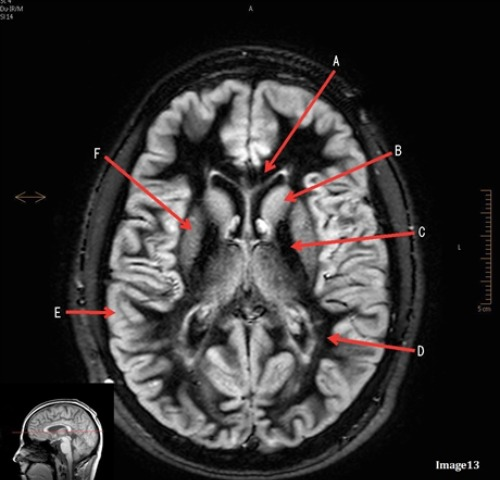

Letter B in image 13 is pointing to:

D. Caudate nucleus

Letter D in Image 13 is pointing to:

B. White matter

Letter C in Image 13 is pointing to:

E. Internal capsule

Letter E in Image 13 is pointing to:

A. Grey matter

Letter F in Image 13 is pointing to:

C. Lentiform nucleus